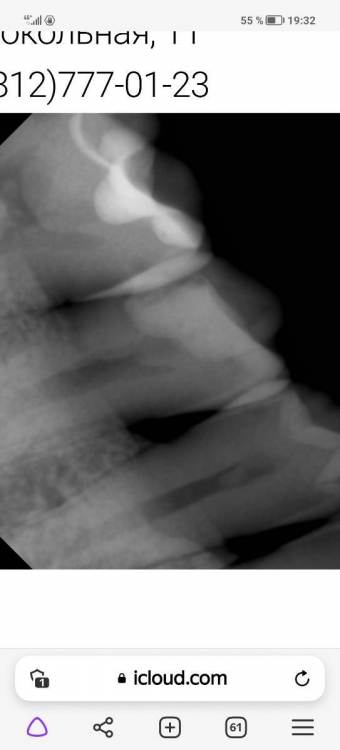

Мне в стоматологии отказались лечить зуб потому что разрушение коронки более 50 %, подскажите, пожалуйста, так ли это? И где это самое разрушение, как его вычислили

если судить только по рентгену, то больше.

Белое на снимке это пломба. Мы не проводим обучение пациентов, но можете посмотреть что такое ИРОПЗ. Я предполагаю, что отказали в лечении по ДМС. Если это так, то стандартные программы не покрывают лечение  таких зубов.